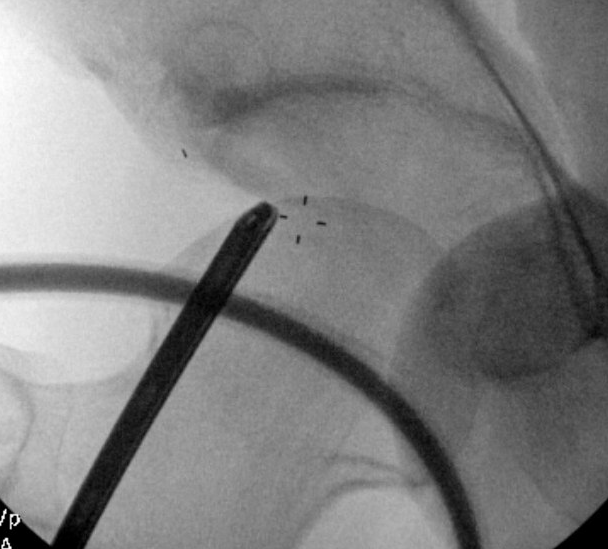

Posterolateral Portal

- 2 cm posterior to GT

- level with superior border GT

- not commonly used

- removal of loose bodies